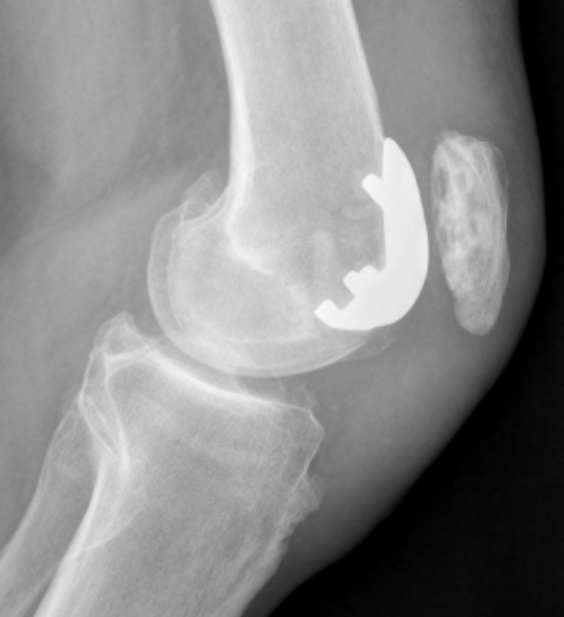

Patellofemoral joint replacement

Technique